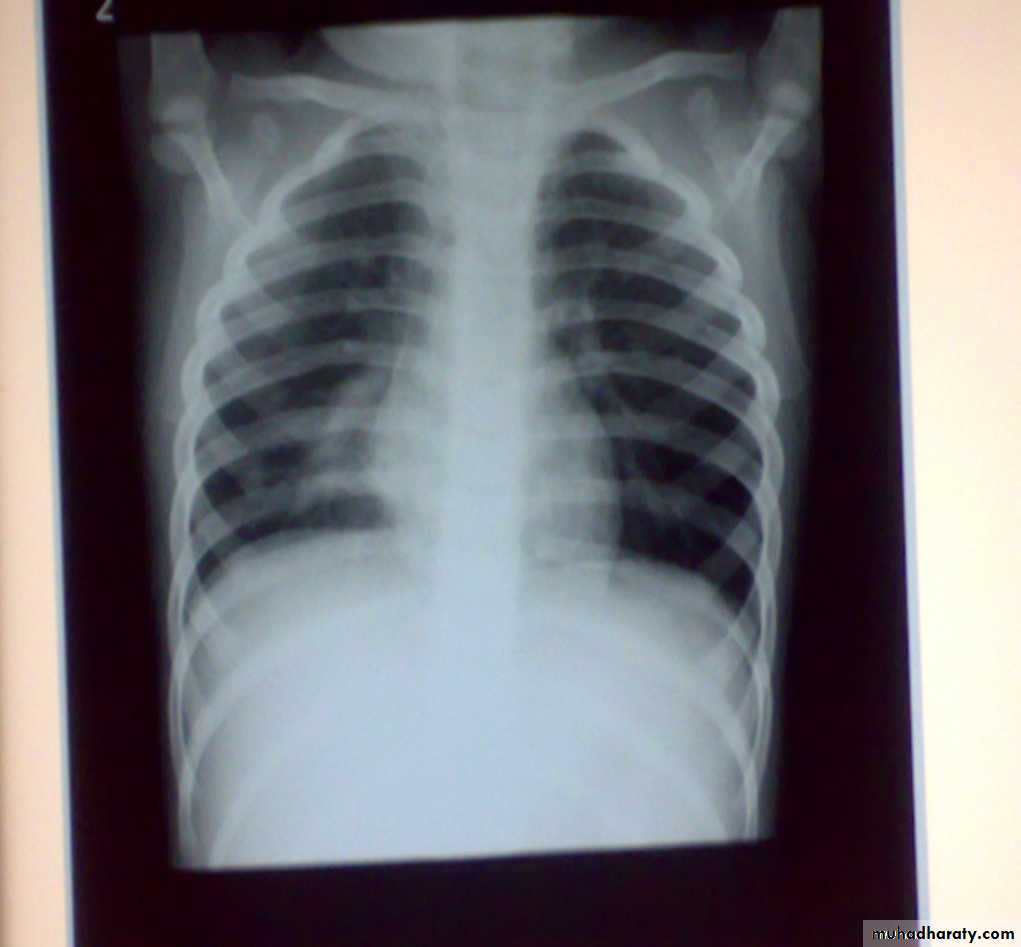

• 4-Pleural effusion

• Is the accumulation of fluid in the pleural space excessive transudation or exudation of the interstitial fluid from the pleural surface. It is signify pleural or systemic disease .

• Its effect depends on its size (mild , moderate or massive ) & the state of the underlying lung .It is classified as transudate when the protein content is less than 3g% or exudates when protein content is more than 3 gm % .Clinically patients will present with dyspnea & pleuritic chest pain

• Radio logically (concave meniscus sign)

• Transudate as in CHF

• Exudate as in malignancy

• Treatment :-1-aspiration (thoracentesis) 2-tube thoracostomy